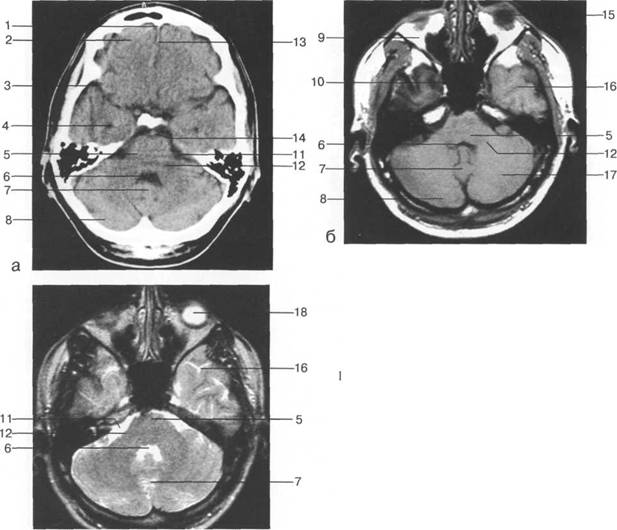

череп 13513u2010n 85;ой ямки, в некоторых случаях хорошо видны лентовидные уплотнения поперечного и III

IV IV IV IV III IV

височная доля; 17 - полушарие мозжечка; 18 - |

Следует остановиться на анатомии подпаутинных пространств задней череп 13513u2010n 85;ой ямки IV 20 мм. Между основанием череп 13513u2010n 72; и нижней поверхностью мозга от большого затылочного отверстия вдоль ската и спинки турецкого седла простирается задняя базальная цистерна. В зави IV

цистерна четверохолмия; 14 -прямой синус; 15 -лобный рог; 16 - головка хвостатого ядра; 17 -перед